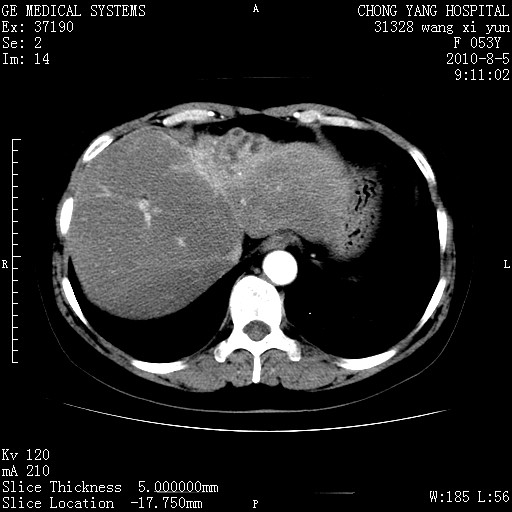

标题: CT28214:F41Y 血尿二十天,建议盆腔平扫加增强。

胆管细胞ca?

1)考虑肝左叶胆管细胞癌。2)脂肪肝。

支持胆管细胞ca。